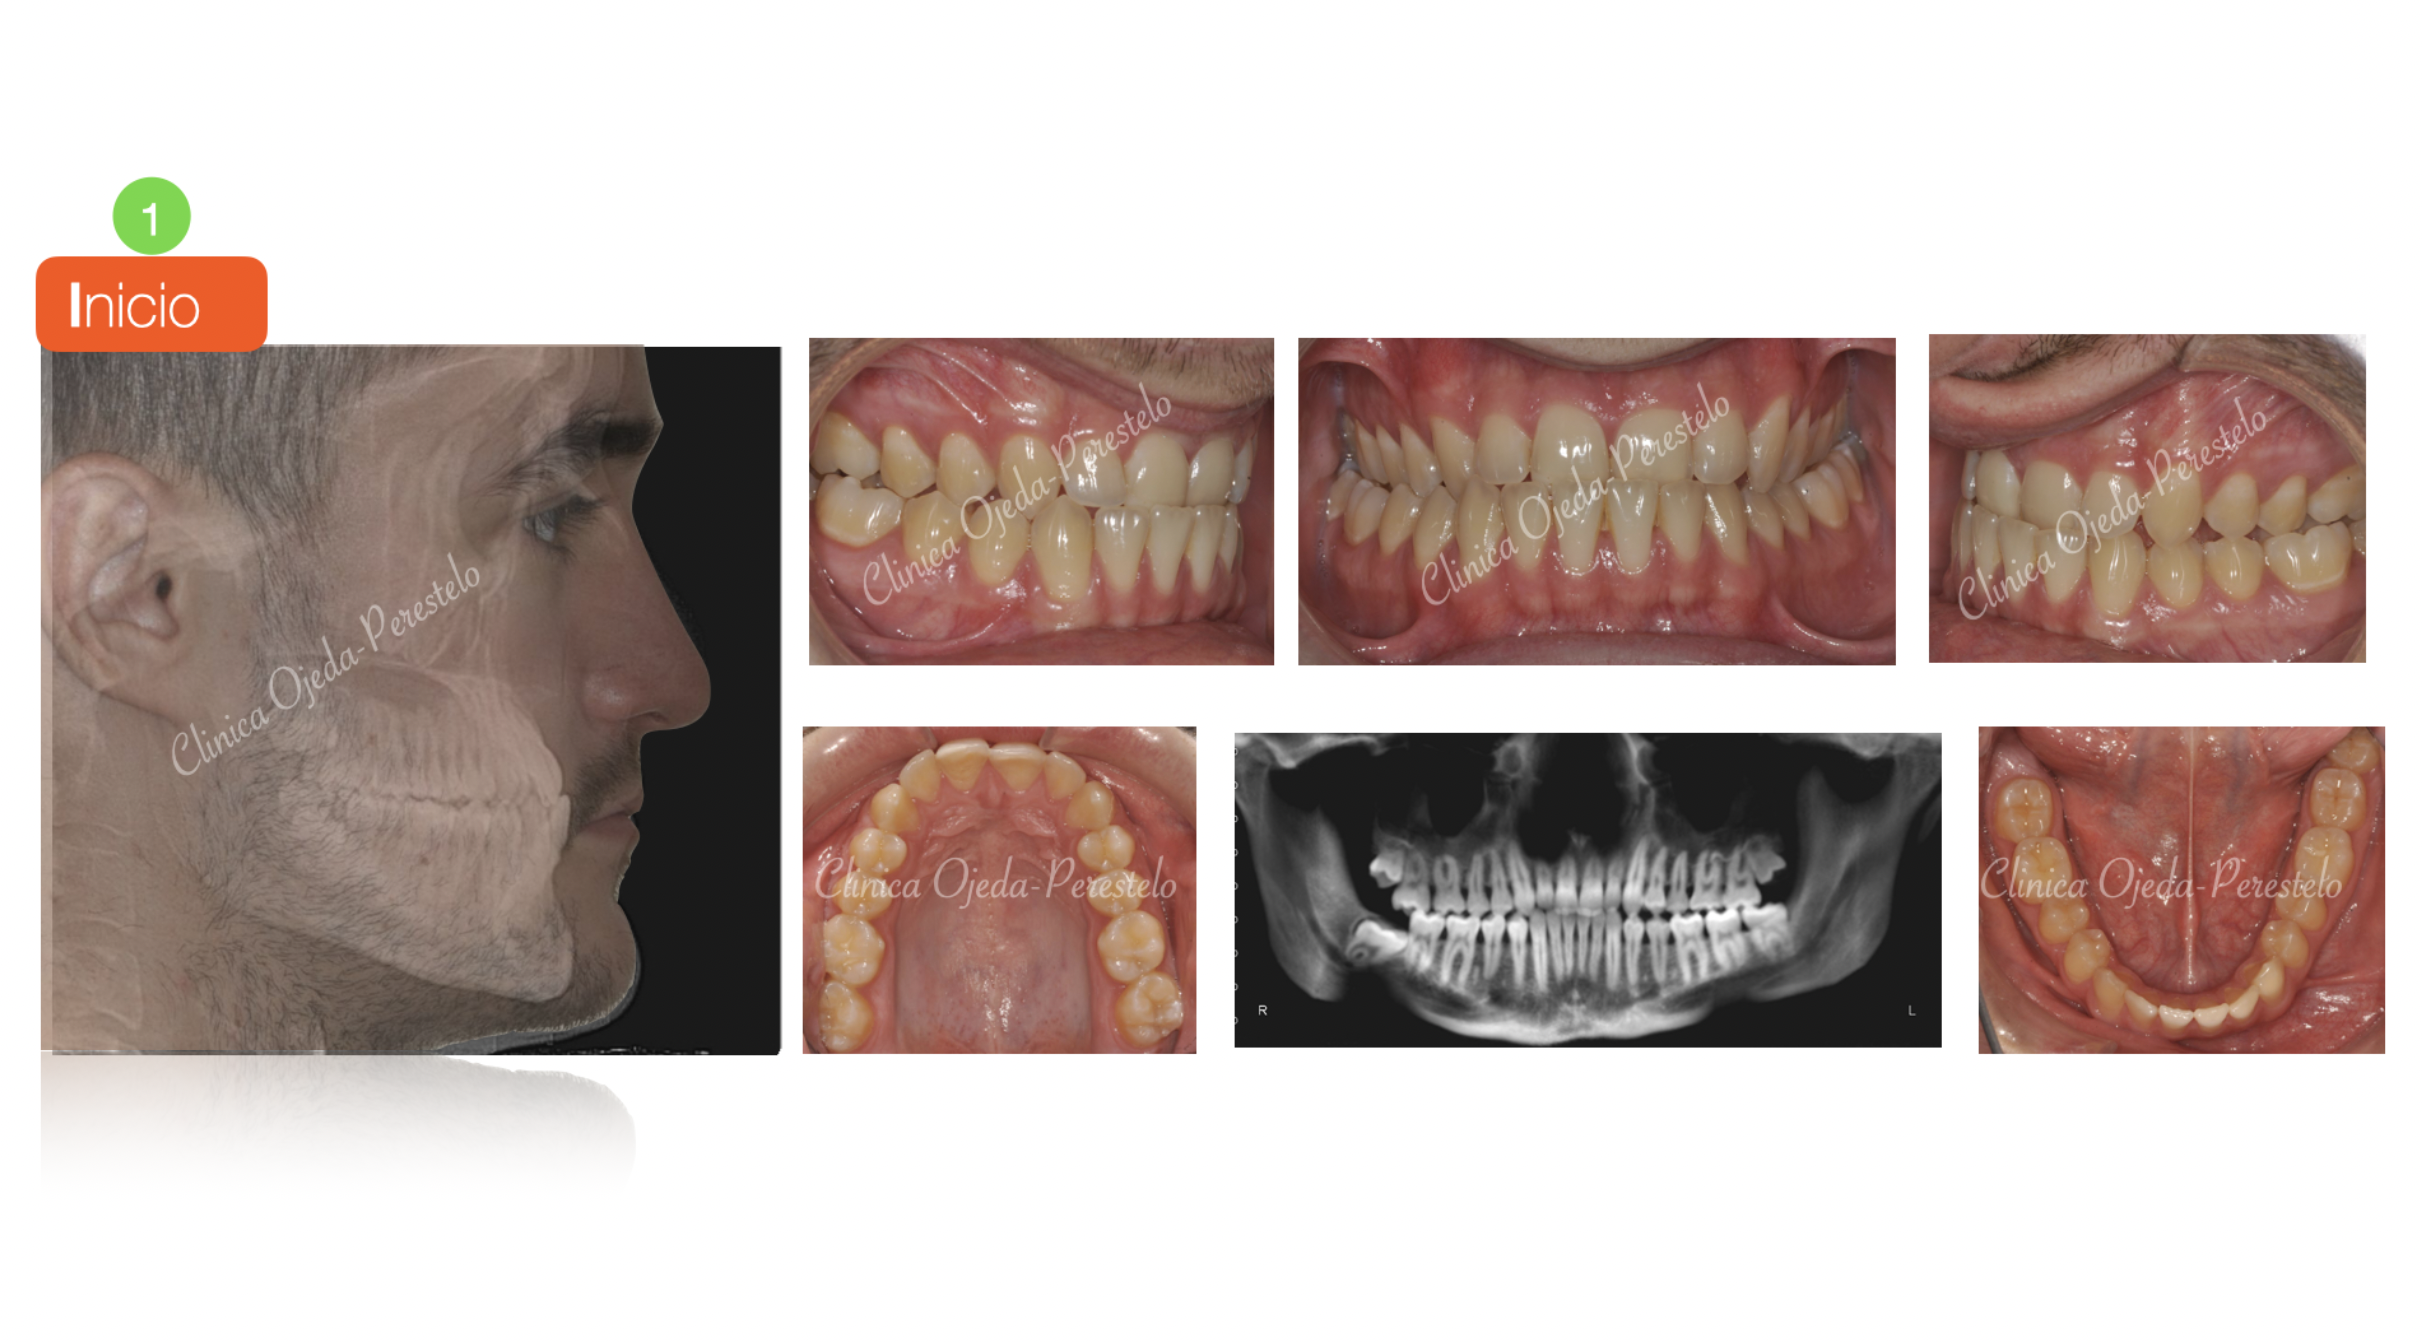

Mordida Invertida en clase III

Los alineadores transparentes nos permiten corregir casos complejos como en este paciente con mordida invertida. Hemos comenzado su tratamiento con la expansión del Maxilar con disyuntor oseosoportado (MARPE) para a continuación comenzar con alineadores en la arcada maxilar y mandibular. Queremos destacar la mejora de la sonrisa así como la consecución de un correcto engranaje dentario con 109 alineadores superiores e inferiores a cambio semanal combinandolo con algo de elásticos intermaxilares.

En la actualidad el paciente está pendiente de comenzar con una serie corta de alineadores con la idea de mejorar la posición del 13 y 21 así como con el ligero espaciamiento presente entre los incisivos inferiores.